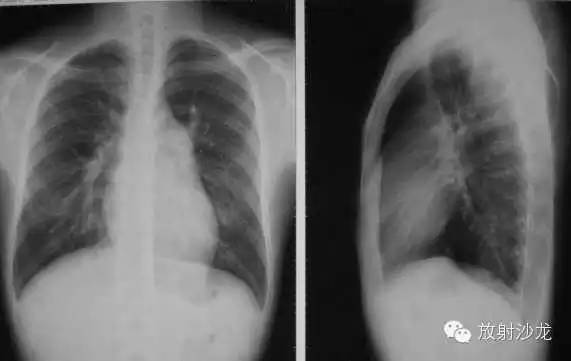

心包炎(pericarditis)

1、心脏向两侧增大,正常心缘弧度消失。

2、腔静脉增宽(体静脉回流右房受阻)。

3、心脏血管比率增大,主动脉影缩短。

4、心缘搏动下降,主动脉搏动正常。

5、肺纹理减少或正常(右心排血量减少)。

6、造影:各心腔无扩张,腔静脉扩张。